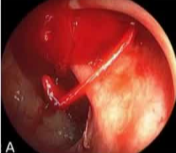

Endoscopy Localization for Empiric Embo

Duodenal ulcer with clot on it |

Empiric GDA embo Bleeding stopped, Hgb stabilized

Endoscopic Clip Localization

Empiric Colonic Embo Case

Bleeding into diverticulum

Region of bleeding tic

Post embo |